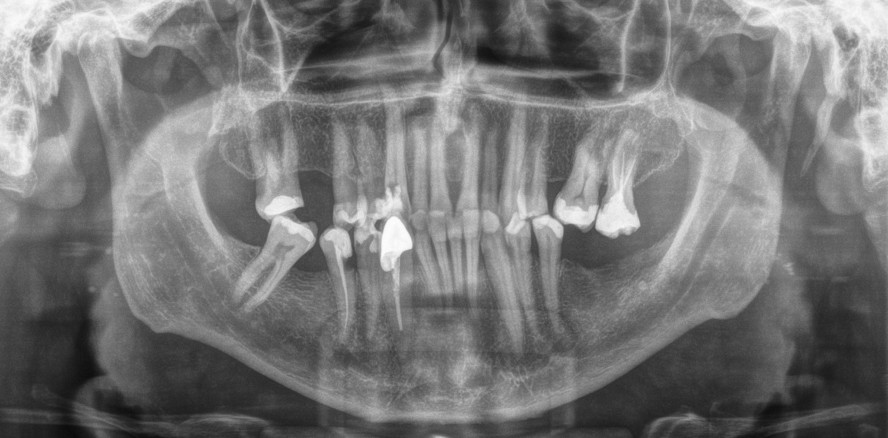

Rekordhalter des längsten menschlichen Zahns der Welt war bislang ein Inder. Diesen Zahn hat Dr. Max Lukas, Zahnarzt in Offenbach am Main, den Indern nun jedoch gezogen – im doppelten Sinne. 37,2 mm misst der neue Rekordhalter. Damit ist der in Offenbach am Main extrahierte Zahn um einen halben Millimeter länger als der bisher gelistete „Riesenzahn“.

Entfernt hatte Dr. Lukas den Zahn des Patienten bereits im Frühjahr. Kein Routineunterfangen, wie er unserer Redaktion verriet: „Der Zahn ließ sich aufgrund seiner Länge nur operativ entfernen. Da dieser von palatinal bereits trepaniert und die Wurzel sehr lang war, musste dennoch behutsam vorgegangen werden, damit es nicht zu einer Wurzelfraktur und damit einer weiterhin erschwerten Zahnentfernung kommen würde.“

Dass es sich bei dem Zahn um einen potenziellen Kandidaten für das Guinnessbuch handeln würde, hatte er im Vorfeld dem OPG entnehmen können, „wenngleich die Statur des Patienten eher unscheinbar war“, so Dr. Lukas.